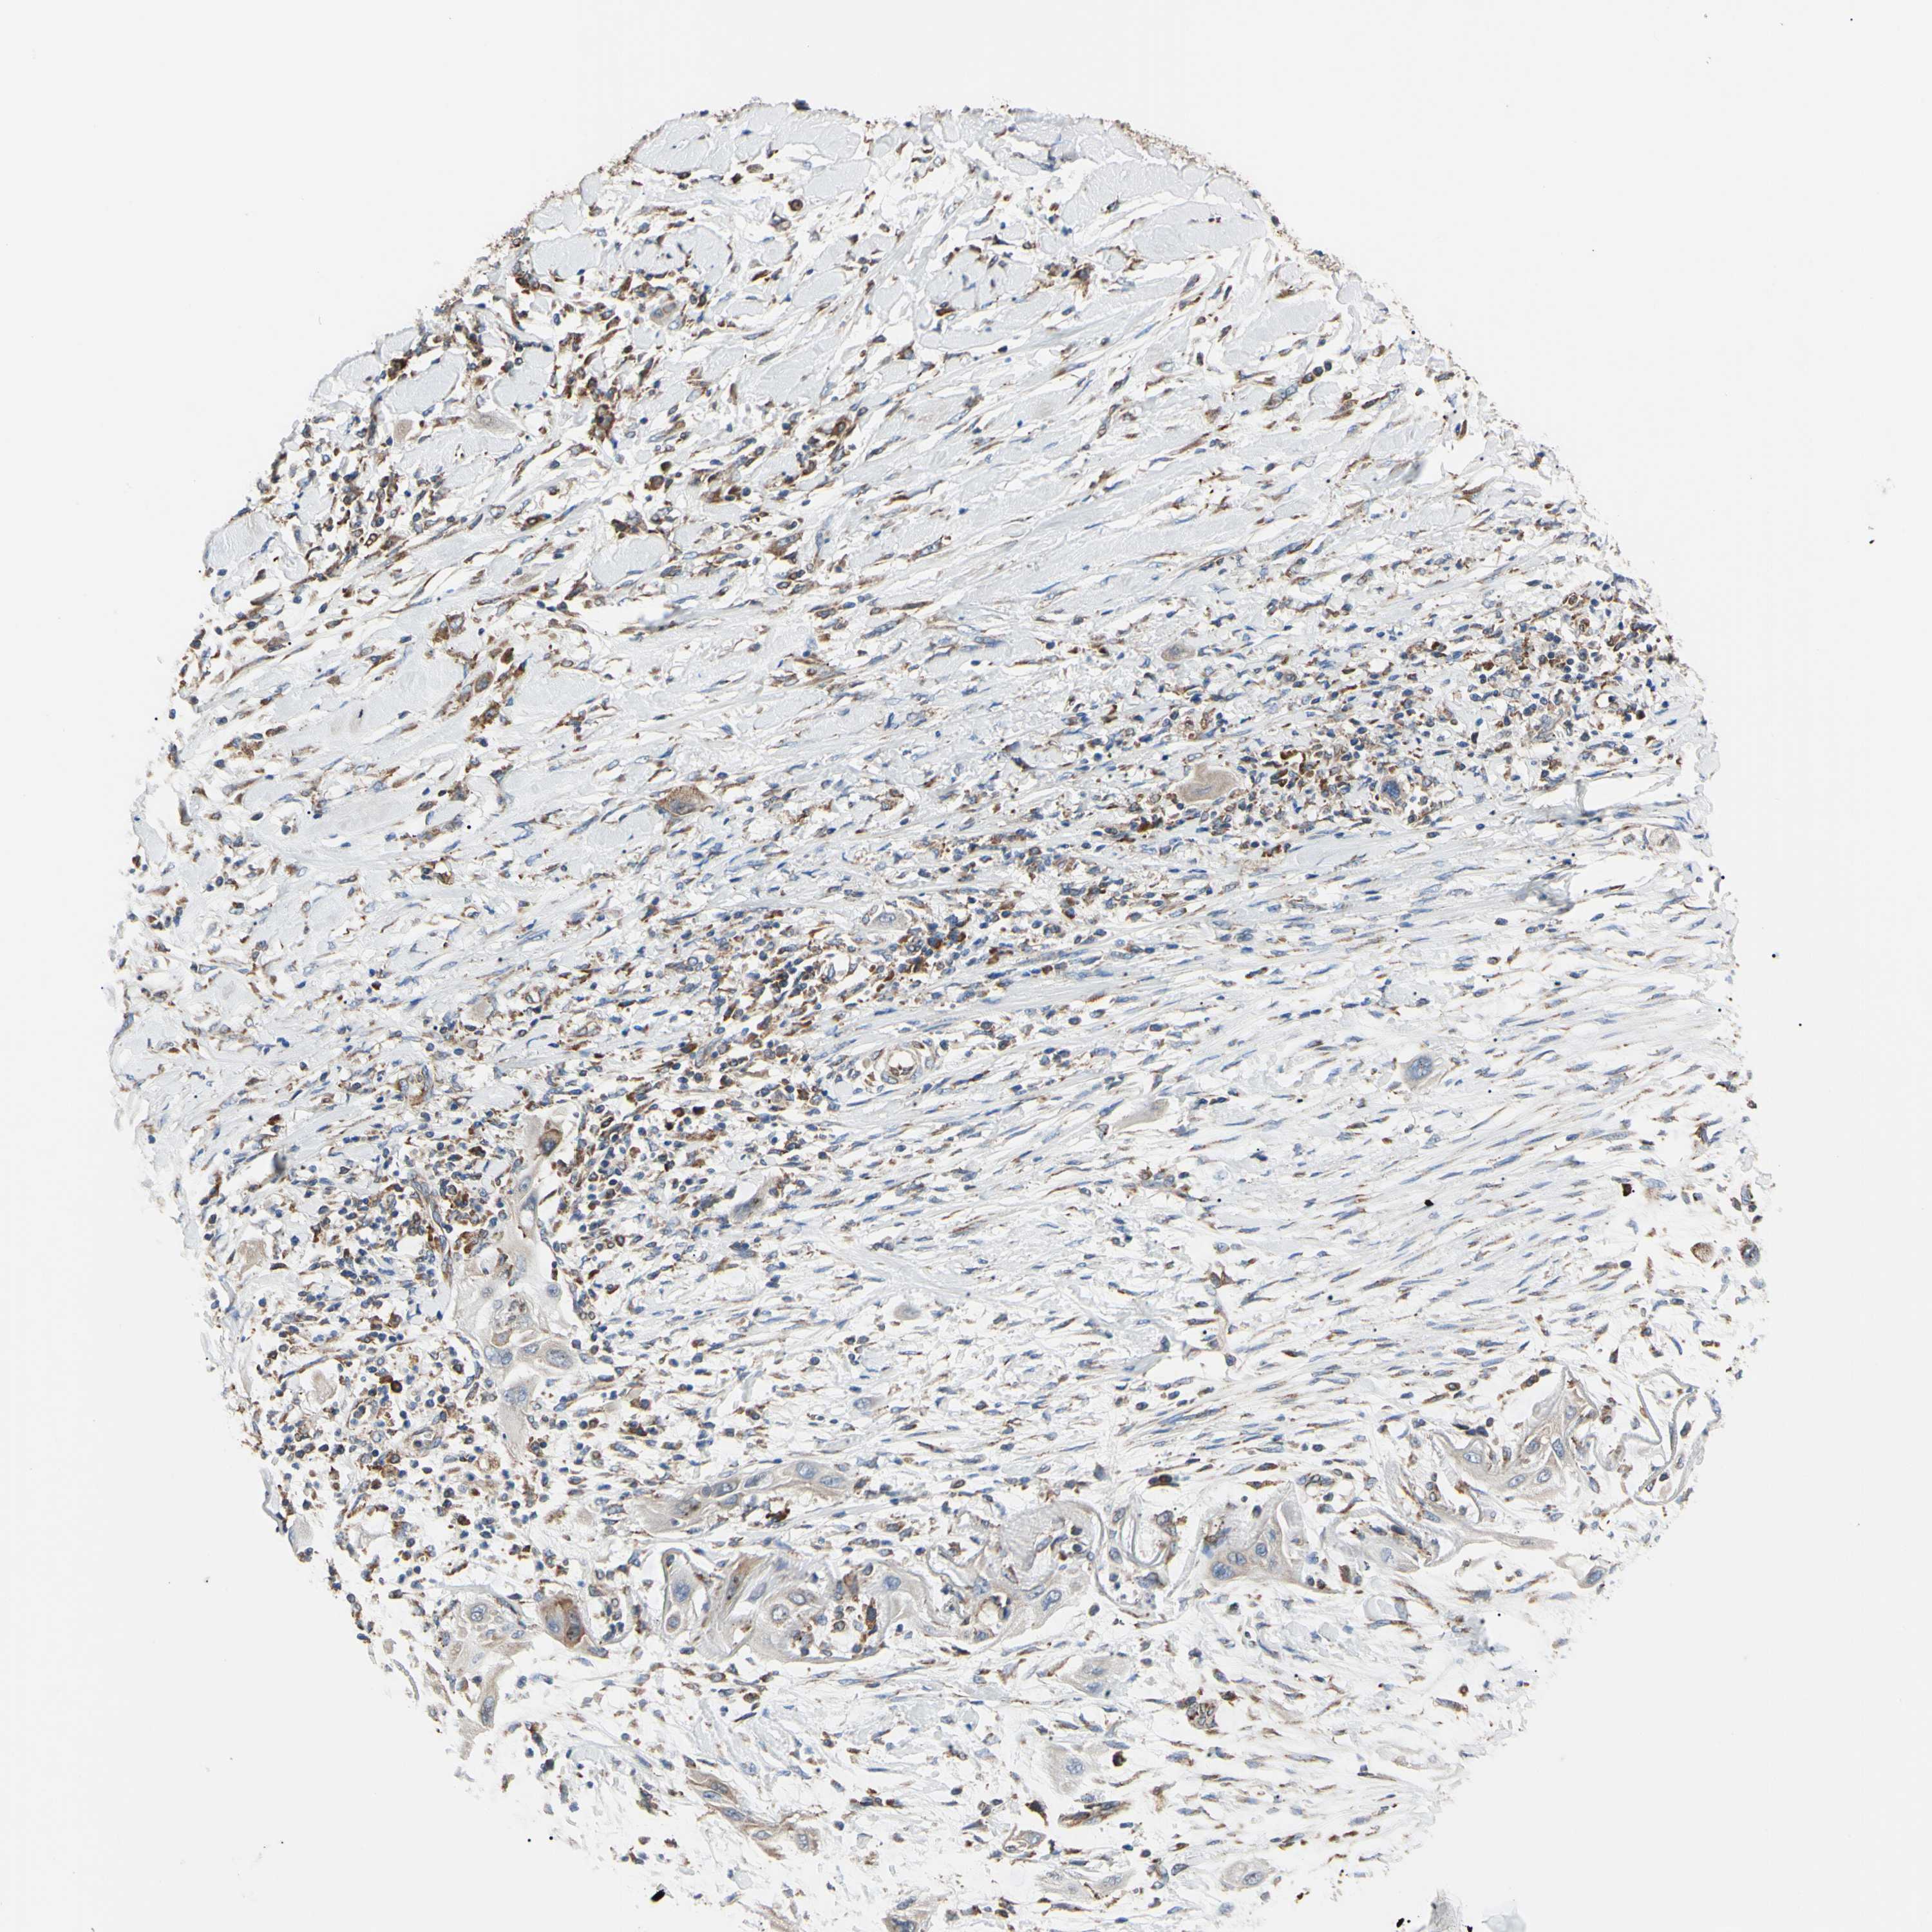

LUNG SQUAMOUS CELL CARCINOMA (TCGA) - Interactive survival scatter ploti

The Survival Scatter plot shows the clinical status (i.e. dead or alive) for all individuals in the patient cohort, based on the same data that underlies the corresponding Kaplan-Meier plots. Patients that are alive at last time for follow-up are shown in blue and patients who have died during the study are shown in red.

The x-axis shows the expression levels (FPKM) of the investigated gene in the tumor tissue at the time of diagnosis. The y-axis shows the follow-up time after diagnosis (years). Both axes are complimented with kernel density curves demonstrating the data density over the axes. The top density plot shows the expression levels (FPKM) distribution among dead (red) and alive patients (blue). The right density plot shows the data density of the survived years of dead patients with high and low expression levels respectively, stratified using the cutoff indicated by the vertical dashed line through the Survival Scatter plot. This cutoff is automatically defined based on the FPKM cutoff that minimizes the p-score. The cutoff can be changed by dragging the vertical line or by entering a cutoff value in the square labeled "Current cut-off".

Under the Survival Scatter plot the p-score landscape (black curve; left axis) is shown together with dead median separation (red curve; right axis). Dead median separation is the difference in median mRNA expression between patients who have died with high and low expression, respectively. It is calculated as follows: median FPKM expression of dead patients with high expression - median FPKM expression of dead patients with low expression. This is intended to aid the user in visually exploring custom cutoffs and the associated p-scores and dead median separation.

Individual patient data is displayed and can be filtered by clicking on one or more of the category buttons on the top of the page. Categories describing expression level and patient information include: high, low, alive, dead, female, male and tumor stages. The scale of the x-axis can be toggled between linear and log-scale by clicking on the "x log" button. Mouse-over function shows TCGA ID, patient information and mRNA expression (FPKM) for each patient.

& Survival analysisi

Kaplan-Meier plots summarize results from analysis of correlation between mRNA expression level and patient survival. Patients were divided based on level of expression into one of the two groups "low" (under cut off) or "high" (over cut off). X-axis shows time for survival (years) and y-axis shows the probability of survival, where 1.0 corresponds to 100 percent.

BMF is not prognostic in Lung Squamous Cell Carcinoma (TCGA)

Best expression cut offi

Based on the FPKM value of each gene, patients were classified into two groups and association between prognosis (survival) and gene expression (FPKM) was examined. The best expression cut-off refers the FPKM value that yields maximal difference with regard to survival between the two groups at the lowest log-rank P-value. Best expression cut-off was selected based on survival analysis .

When clicking on this number, the vertical dashed line indicating cut-off, the interactive survival plot, and the Kaplan-Meier curve will be adjusted to show results based on the best expression cut-off.

: 3.73

Median expressioni

Median expression refers to the median FPKM value calculated based on the gene expression (FPKM) data from all patients in this dataset. When clicking on this number, the vertical dashed line indicating cut-off, the interactive survival plot, and the Kaplan-Meier curve will be adjusted to show results based on the median expression.

: N/A

Median follow up timei

Median follow up time refers to the median time (years) after diagnosis with this type of cancer, based on clinical data from all patients in this dataset.

P scorei

Log-rank P value for Kaplan-Meier plot showing results from analysis of correlation between mRNA expression level and patient survival.

N/A

5-year survival highi

5-year survival for patients with higher expression than the expression cutoff.

For melanoma and glioma, 3-year survival is shown.

5-year survival lowi

5-year survival for patients with lower expression than the expression cutoff.

TCGA RNA samplesi

RNA-seq data is reported as average FPKM (number Fragments Per Kilobase of exon per Million reads), generated by the The Cancer Genome Atlas (TCGA) .

Normal distribution across the dataset is visualized with box plots, shown as median and 25th and 75th percentiles. Points are displayed as outliers if they are above or below 1.5 times the interquartile range. FPKM values of the individual samples are presented next to the box plot.

Average pTPM 9.9

Number of samples 489